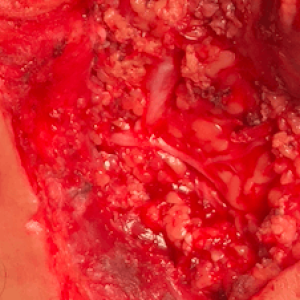

Employing the same prototype axon imaging system previously documented to markedly enhance nerve visualization in both in vivo animal and ex vivo human models, surgical fields were observed in 17 patients under both white and NUV light during parotid tumor resection (n = 3), thyroid tumor resection (n = 7), and surgery for peripheral nerve and spinal tumors and injury (n = 7).

In all 17 patients, the intra-operative use of the imaging system both was feasible and markedly enhanced the localization of all neural tissues throughout their course within the surgical field. All 17 procedures were successful and devoid of any peri-operative complications or post-operative neurological deficits.